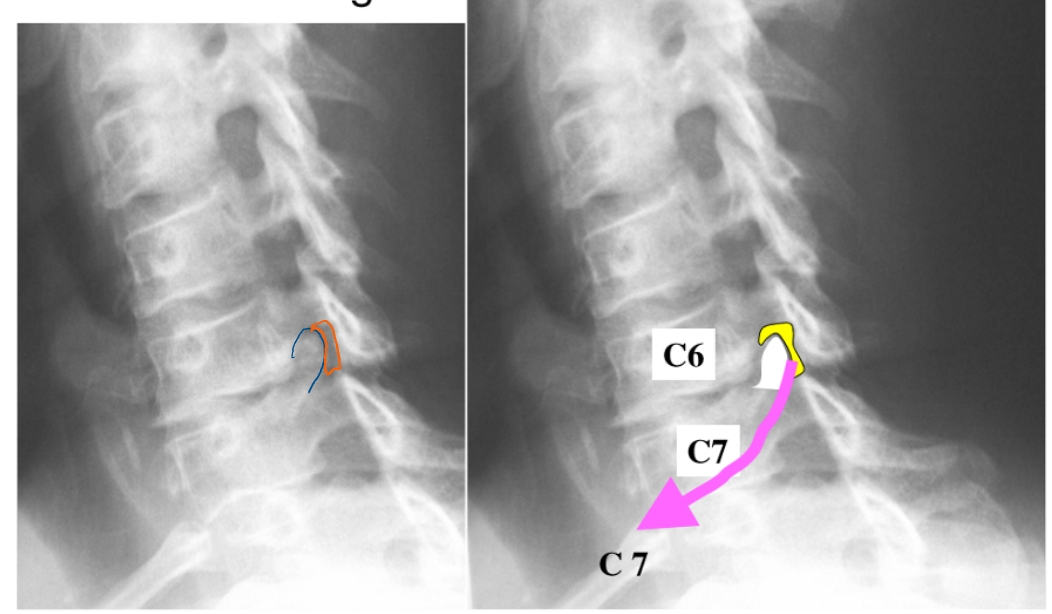

= uncartrose C6-C7 (links)

klachten: cervico-brachialgie

blauw gedeelte = osteofiet

pijn straalt uit naar 2e, 3e en radiale helft 4e vinger